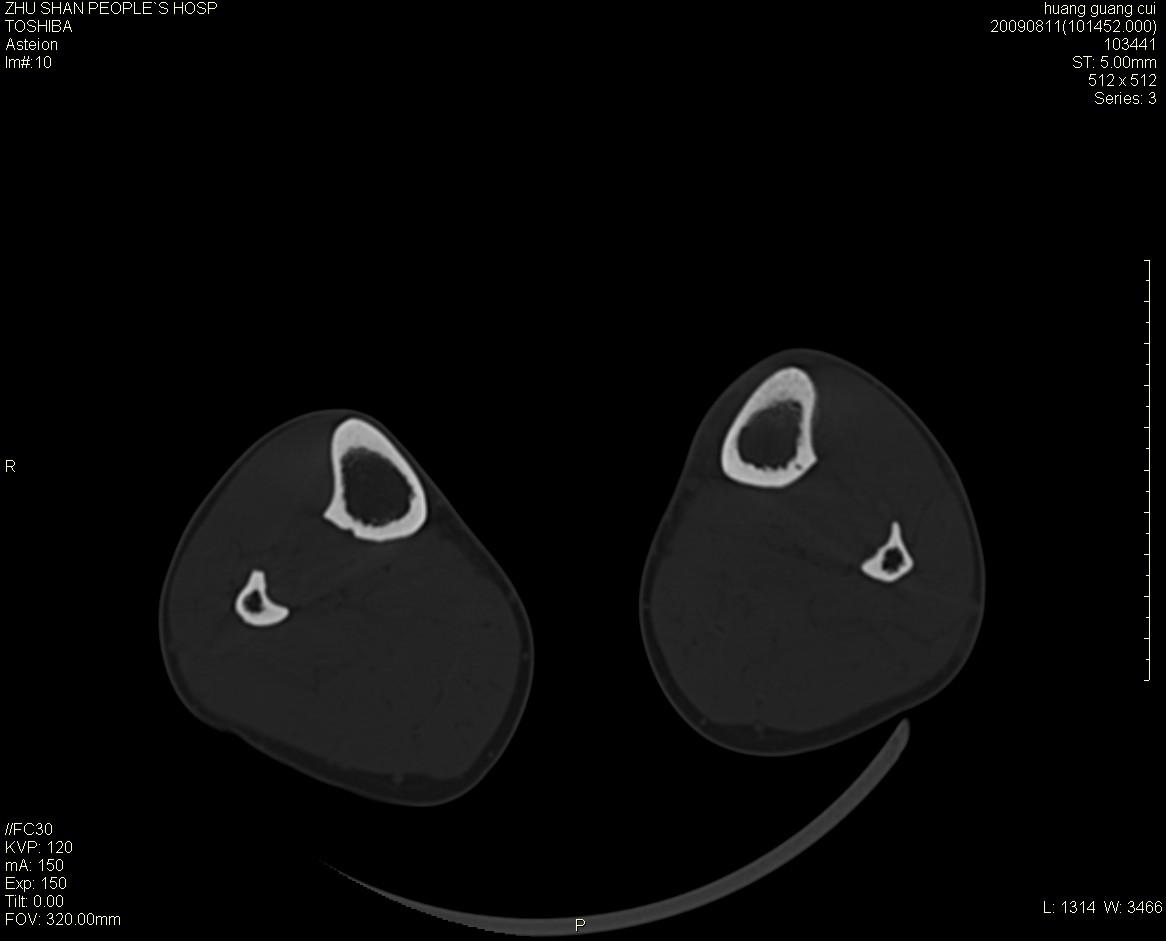

左侧胫骨中段骨皮质溶骨性破坏,髓腔内外见软组织肿块,无明显钙化及成骨,定位相显示病变周围“筛孔样”改变,定性恶性无疑,原发或转移均有可能,倾向于骨纤维肉瘤可能性大,转移瘤不排除。膝关节以下骨转移很少,且要有原发灶支持,尤文氏肉瘤年龄太大不支持。